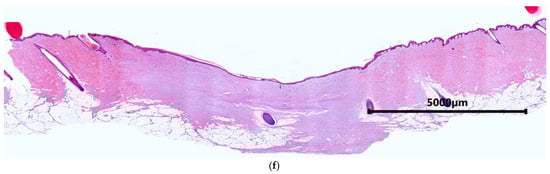

2. Results and Discussion

2.2. Characteristics of the Wound Defect Condition on Day 42 of the Study

3.11. Morphological Studies of Biomaterial

3.11.1. Light Microscopy

3.11.3. Morphometric Examinations